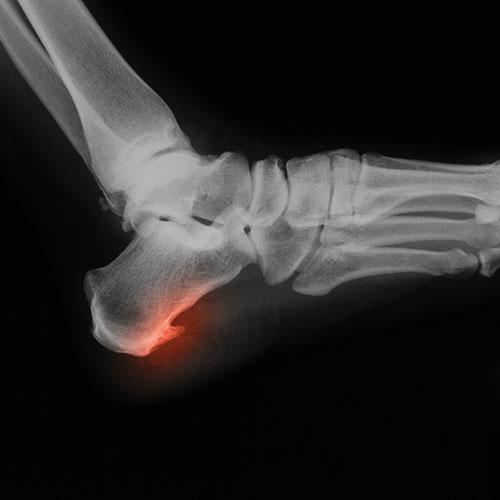

Heel spurs are calcium deposits on the bottom of the heel bone and they can feel like a nail poking into your heel. There are a number of factors that can contribute to straining of the muscles and ligaments in the foot, which is the chief cause of heel spurs. The main factors are excess weight, poor fitting shoes, overuse (often seen in athletes), and gait abnormalities.

Heel spur symptoms include heat radiating from the heel, a shooting pain when standing up and a dull ache throughout the day, inflammation in the ball of the foot, and a visible protrusion at the heel.